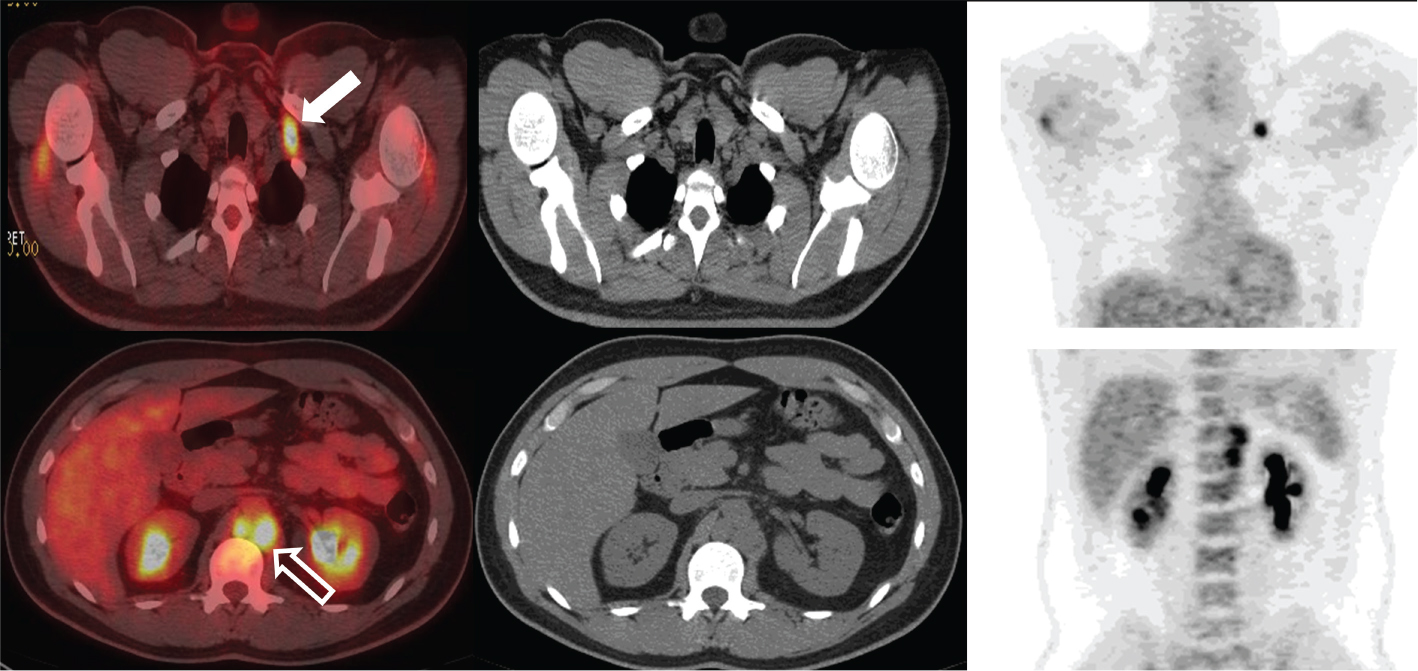

Fig 3

Figure 3. Seminal vesicles. FDG PET/CT demonstrates uptake within the bilateral seminal vesicles (thick solid arrows) in one patient (row 3A) and within an enlarged right seminal vesicle (thick solid arrow) in another patient (row 3B). Biopsy was negative in the first patient suggesting that activity likely represented urinary reflux of radiotracer (3A). Biopsy was positive for a plasmacytoma in the second patient (3B).

Involvement of the seminal vesicles is generally secondary. The most common neoplastic involvement of the seminal vesicles is direct extension of metastasis from prostate, bladder, or rectal cancer, often present upon the initial examination. Metastases from malignancies such as Merkel cell, lymphoma, and hepatocellular cancer have been seen. We present a documented case of plasmacytoma in a seminal vesicle (Figure 3B). Primary malignant neoplasms of the seminal vesicles are relatively rare: adenocarcinoma, sarcoma, leiomyosarcoma, and angiosarcoma are among those noted. A review of the literature showed only approximately 60 reported cases of adenocarcinoma of the seminal vesicles (1619). In the presence of an adjacent malignancy such as prostate cancer, direct extension should be considered. In other settings, metastatic disease or primary seminal vesicle cancer should be considered. As PET/CT findings are usually incidental, there are no established protocols/guidelines for PET/CT imaging of seminal vesicles.